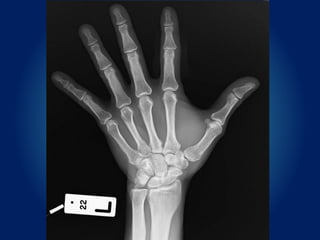

ผู้ป่วยชายไทย อายุ 51 ปี

Chief complaint : แผลฉีกขาดที่นิ้วมือซ้าย 4 ชั่วโมงก่อนมา รพ.

Present illness : 4 ชั่วโมงก่อนมารพ. ผู้ป่วยถูกเคียวบาดนิ้วชี้มือซ้าย มี

เลือดออก ขยับนิ้วชี้ได้ไม่มีแผลที่นิ้วอื่นๆ

Left index finger

• Lacerated wound 2x1 cm

• Can flex and extend MP jt

• Can flex PIP and DIP jt.

• Capillary refill < 2 secs